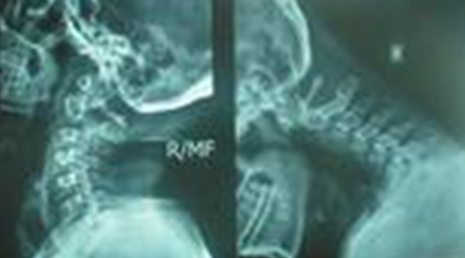

Degenerative Spine

The phrase "degenerative changes" in the spine refers to osteoarthritis of the spine. Osteoarthritis is the most common form of arthritis. Doctors may also refer to it as degenerative arthritis or degenerative joint disease.